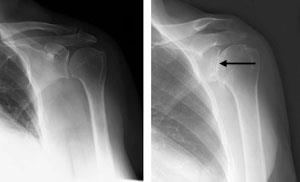

Reverse total shoulder replacement

An X-ray of a reverse total shoulder replacement.

Rotator cuff arthropathy and reverse total shoulder replacement

(Left) Rotator cuff arthropathy. (Right) The reverse total shoulder replacement allows other muscles — such as the deltoid — to do the work of the damaged rotator cuff tendons.